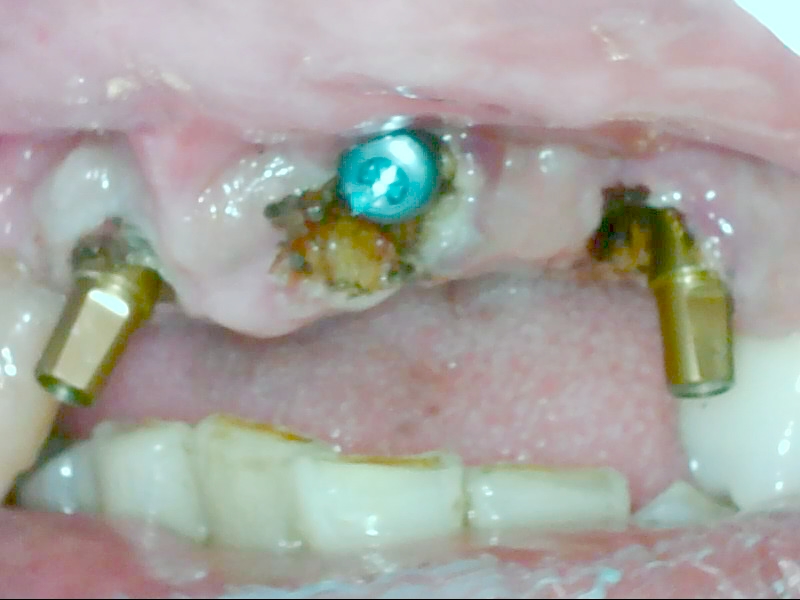

治療中

上の写真はオペの日に抜歯をしてインプラント体を入れる抜歯即埋入です。